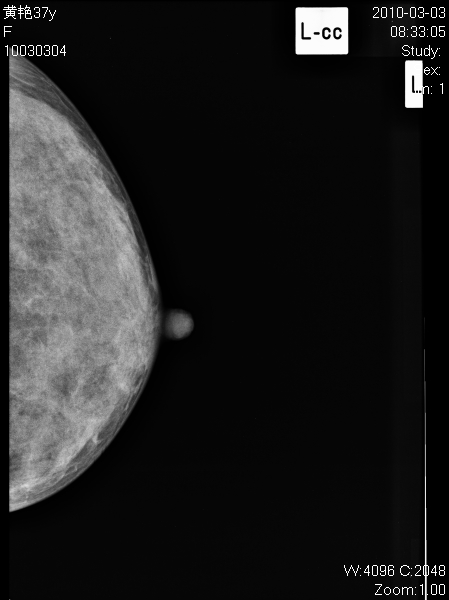

以下是引用子期在2010-3-23 8:29:00的发言:[br]右乳肿块,边缘毛糙,内见砂砾状钙化,考虑乳癌。[br]少了一张片啊。

以下是引用拾荒者在2010-3-23 20:04:00的发言:[br]右乳肿块,边缘毛糙,境界不清,内见多发砂砾状钙化,考虑浸润性导管癌可能。

以下是引用37度在2010-3-24 11:00:00的发言:[br]右乳肿块,边缘毛糙,内见砂砾状钙化,考虑乳癌。